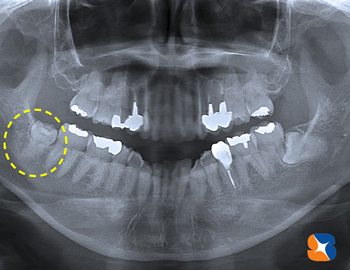

左写真は、お口全体のレントゲン。

早速、レントゲン撮影をして確認。歯の頭はアゴ骨(=写真①=)が、歯の根は弯曲している(=写真②=)ため、親知らずが正位置まで放出できなかったと推測。